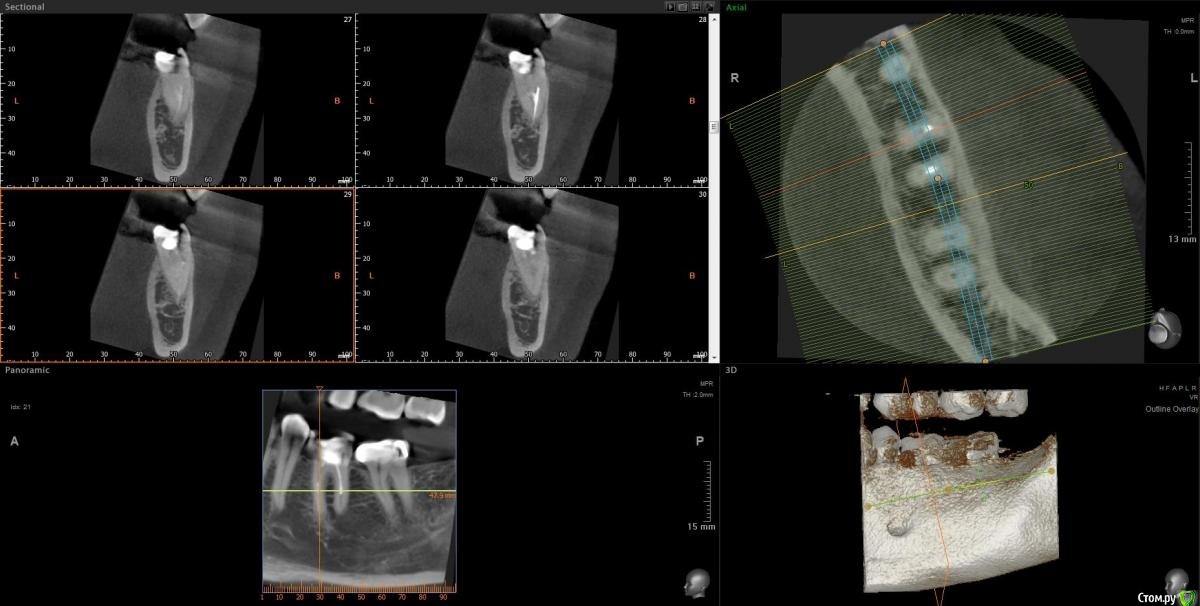

Slava76 Опубликовано 5 декабря, 2020 Поделиться Опубликовано 5 декабря, 2020 Всем доброго дня!Три дня назад с утра появилась боль в нижней челюсти слева. Сначала было не понятно, что болит зуб или мышцы. Но боль шла из под двух крайних коренных зубов. На крайнем зубе коронка, которую установил пару лет назад, зуб живой. У другого зуба пломба, которую установили около 10 лет назад, нервы удалены. Постучал чайной ложкой по этим зубам, боль не усилилась. От холодного, горячего боль так же не усиливается. К вечеру небольшая боль ощущалась только при сжимании зубов. На следующий день с утра все повторилось, с утра болело сильней, к вечеру слабей. Сходил на прием к стоматологу. Сделали снимок, см. вложение. Врач сказал, что у крайнего зуба коронка стоит хорошо, но под коронкой в зубной ткани он видит трещину. Для того, чтобы понять действительно ли она есть и какого размера посоветовал сделать КТ. У зуба под пломбой один канал не долечен, в другом сломали медицинской инструмент. Каких то воспалений он не увидел. Он считает, что боль может вызывать как один, так и другой зуб. Если есть трещина под коронкой, то вылечить зуб нельзя. Только удаление. Если "виноват" зуб под пломбой, то можно перелечить каналы и поставить коронку. В итоге сказал немного подождать, если боль не пройдет, то делать КТ и уже решать. Боль не проходит. Она не сильная, не стреляющая, терпеть ее легко. По ощущениям кажется, что боль идет от зуба под коронкой, но не уверен. Что посоветуете делать дальше? Врач, у которого был, достаточно молод. Хочется услышать еще одно мнение.Заранее благодарю за советы! Ссылка на комментарий

Slava76 Опубликовано 5 декабря, 2020 Автор Поделиться Опубликовано 5 декабря, 2020 (изменено) Почему-то не подгрузился снимок. ДобавляюЕще добавлю снимок всех зубов, который делали в 2016 г. Изменено 5 декабря, 2020 пользователем Slava76 Ссылка на комментарий

Slava76 Опубликовано 7 декабря, 2020 Автор Поделиться Опубликовано 7 декабря, 2020 (изменено) Сегодня сделал КТ. Выложил здесь https://cloud.mail.ru/public/2ezX/2HwT6HocyНа вечер записался к другому врачу. Послушаю, что он скажет.До обеда при нажатие была небольшая боль. Сейчас практически ее не чувствую. И так уже 4 дня. P.s.1 очень боюсь начать лечить не тот зуб. Коронку очень не хочется трогать. Ей все два года. Делала ее очень хороший врач.P.s.2 может само все пройдет... Изменено 7 декабря, 2020 пользователем Slava76 Ссылка на комментарий

Slava76 Опубликовано 7 декабря, 2020 Автор Поделиться Опубликовано 7 декабря, 2020 Вернулся от врача. Он посмотрел КТ и подтвердил слова DmitrySH. На 90% врач уверен, что проблема из-за не до конца залеченного канала и сломанного инструмента. Сказал, что нужно лечение под микроскопом. У них в поликлинике таких специалистов нет. Завтра начну искать такого врача в Нижнем Ссылка на комментарий

wladdX Опубликовано 7 декабря, 2020 Поделиться Опубликовано 7 декабря, 2020 (изменено) Трещины в зубе 37 не увидел Изменено 7 декабря, 2020 пользователем wladdX Ссылка на комментарий